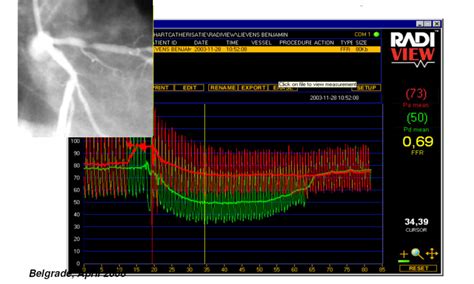

Fractional Flow Reserve (FFR) is a minimally invasive diagnostic technique used during coronary angiography to assess the physiological significance of coronary artery stenoses (narrowings). It measures the pressure difference across a stenosis to determine whether it is causing a significant reduction in blood flow to the heart muscle. This information helps cardiologists decide whether to perform revascularization (e.g., angioplasty or bypass surgery) to improve blood flow or to manage the patient with medical therapy alone. FFR is based on the principle that a stenosis that significantly reduces blood flow will have a lower pressure distal (downstream) to the narrowing compared to the pressure proximal (upstream) to the narrowing. The FFR value is calculated as the ratio of the distal coronary pressure to the proximal coronary pressure during maximal hyperemia (increased blood flow). An FFR value of 0.80 or less indicates that the stenosis is causing a significant reduction in blood flow and that revascularization is likely to be beneficial. Conversely, an FFR value above 0.80 suggests that the stenosis is not significantly affecting blood flow and that medical therapy may be sufficient. FFR has been shown to improve clinical outcomes and reduce the need for unnecessary revascularization procedures compared to angiography alone. It is now a standard of care in many cardiology practices for the evaluation of coronary artery disease. By providing objective, physiological data, FFR helps cardiologists make informed decisions about the best course of treatment for their patients, ultimately improving their quality of life and reducing the risk of adverse cardiac events.

2. Measuring Pressure: Now, here’s where FFR comes in. A special wire with a pressure sensor at its tip is advanced through the catheter and positioned across the narrowed section of the artery. This wire can measure the blood pressure before (proximal) and after (distal) the blockage.

4. Calculating the FFR: During hyperemia, the pressure sensor measures the pressure on both sides of the blockage. The FFR is calculated as the ratio of the pressure after the blockage to the pressure before the blockage. So, it’s a simple division: Pressure Downstream / Pressure Upstream.

5. Interpreting the Results: This is where the magic happens. The FFR value is a number between 0 and 1. Here’s what it means:

• FFR > 0.80: This usually means the blockage isn’t significantly affecting blood flow. You might not need a stent or angioplasty, and medication might be enough.

• FFR ≤ 0.80: This suggests the blockage is significantly reducing blood flow. In this case, a procedure to open the artery, like angioplasty with stenting, is often recommended to improve blood flow and reduce symptoms.